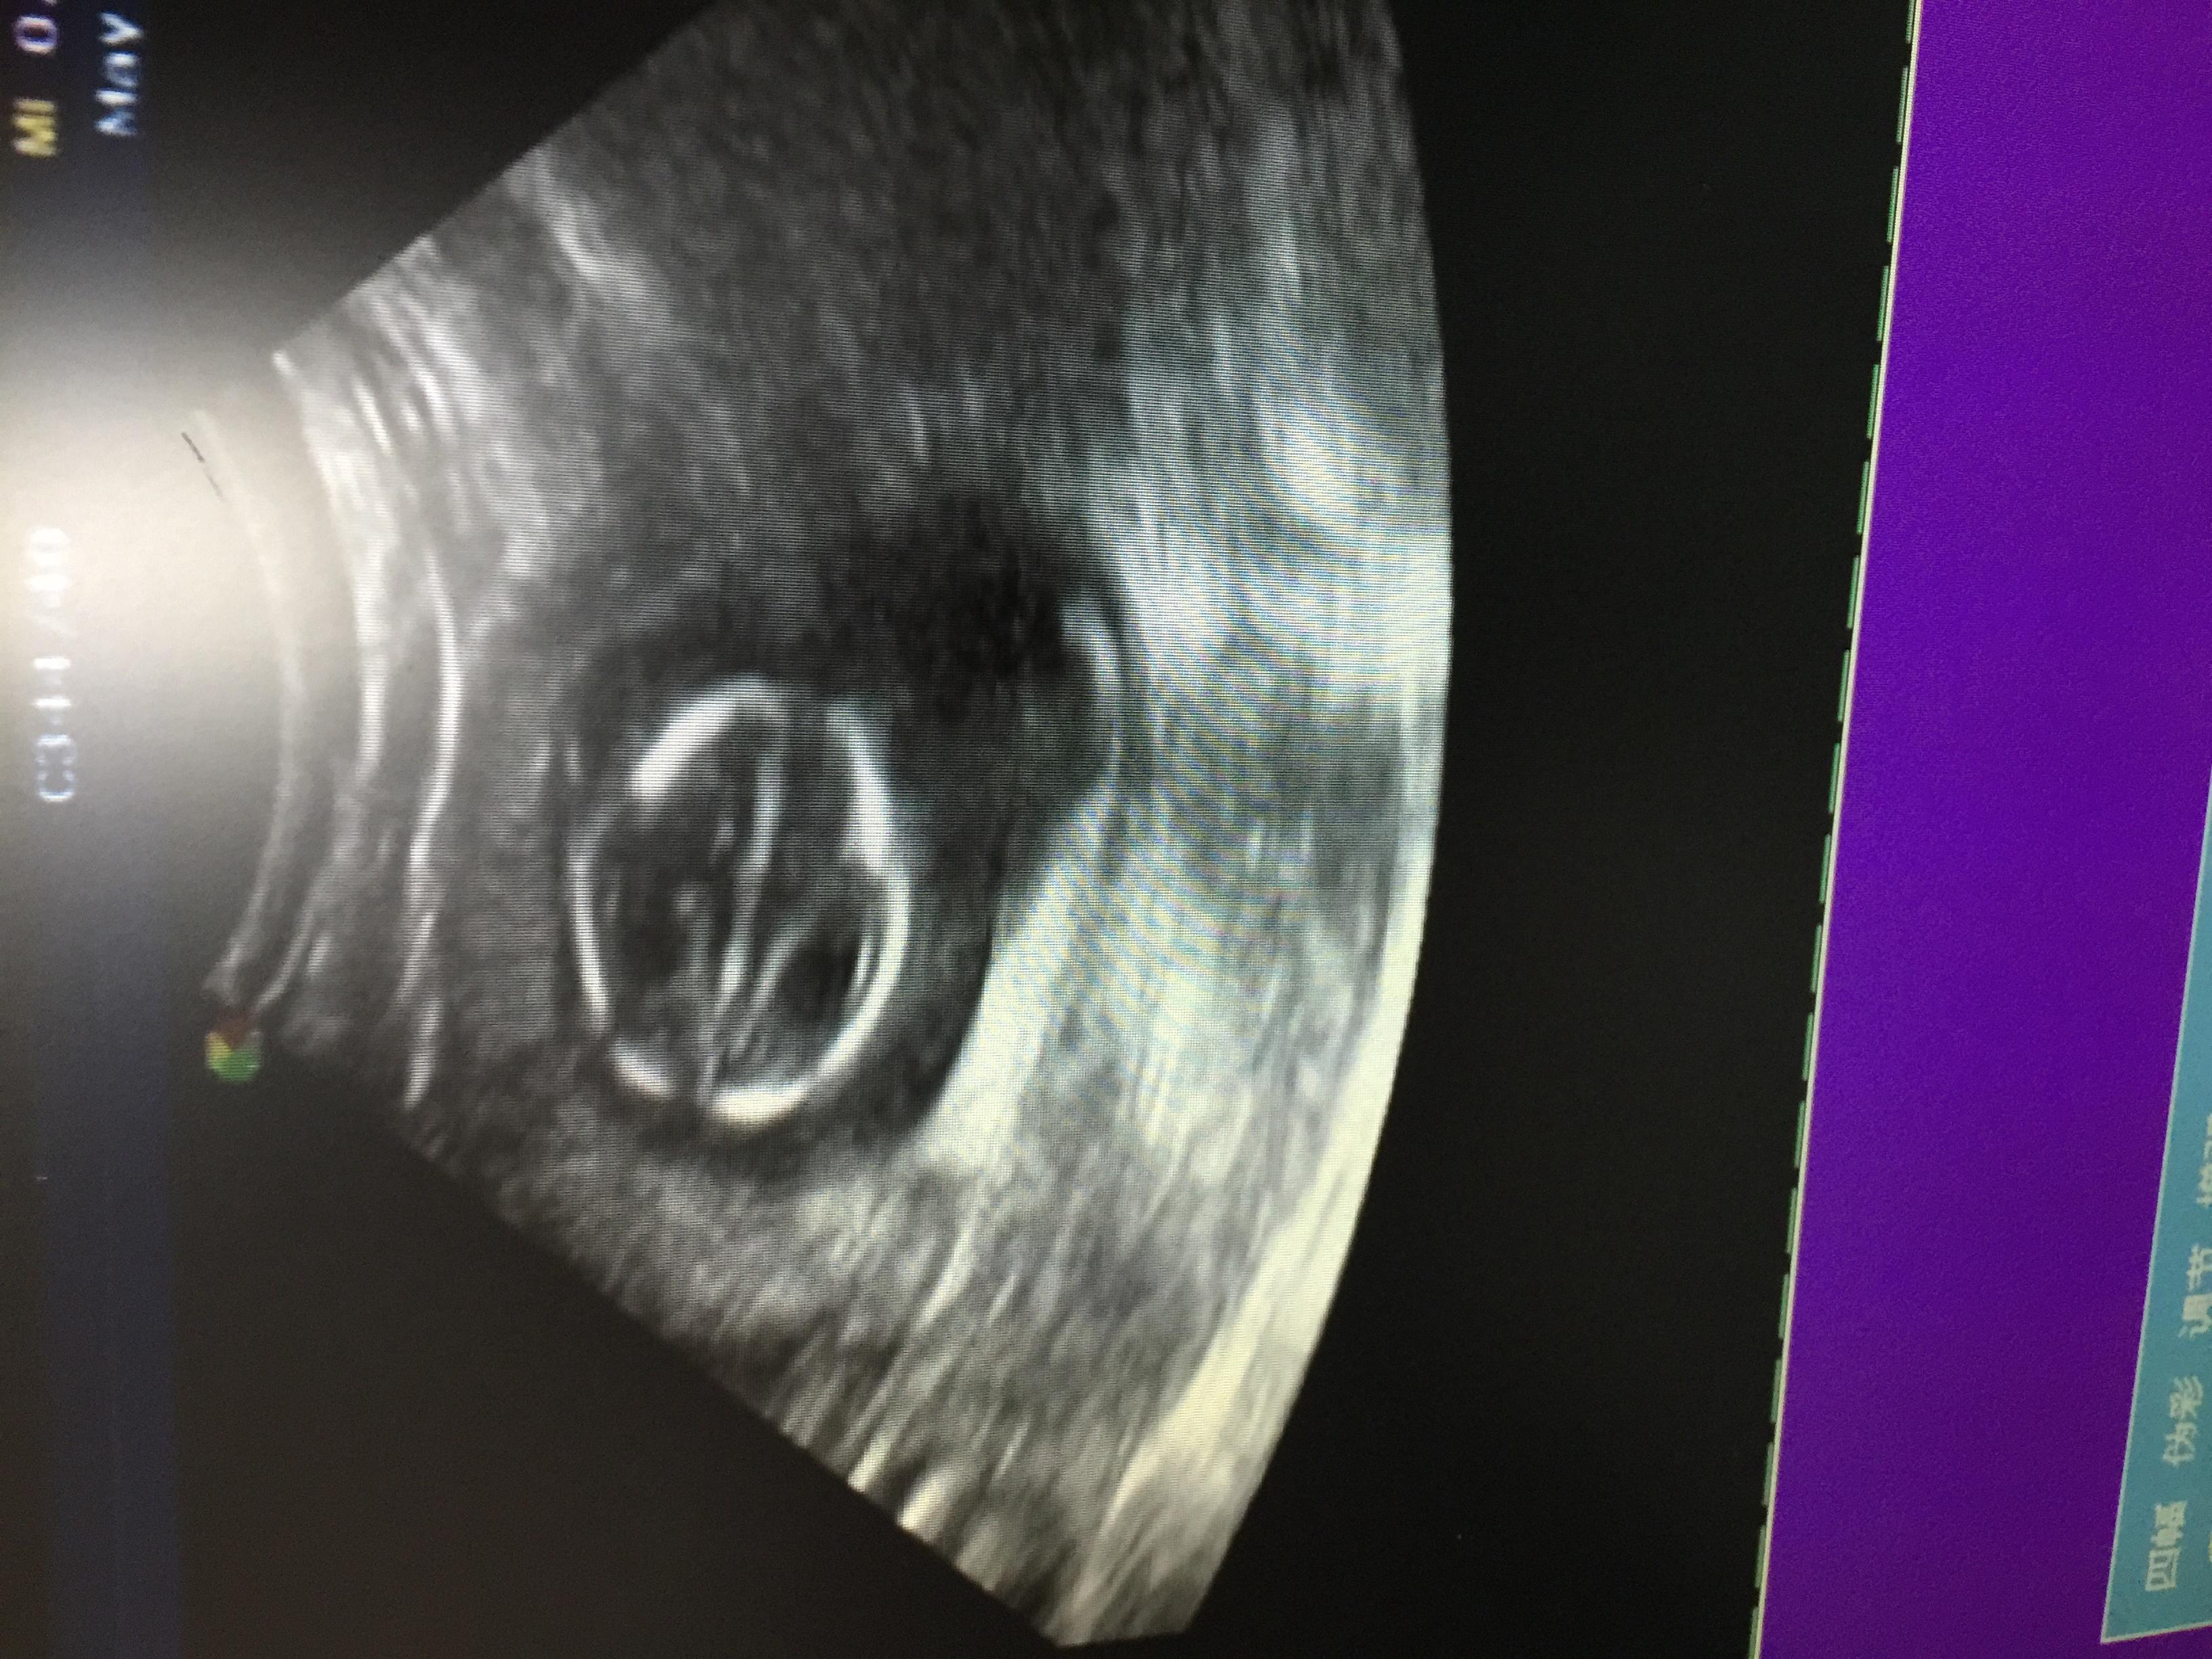

这个胎儿大脑有问题吗

图片尺寸3264x2448

脑电图小妹妹的脑彩超大家帮看看